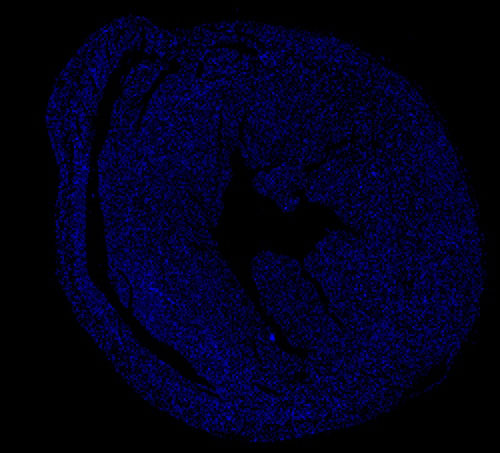

DAPI染色-小鼠心臟